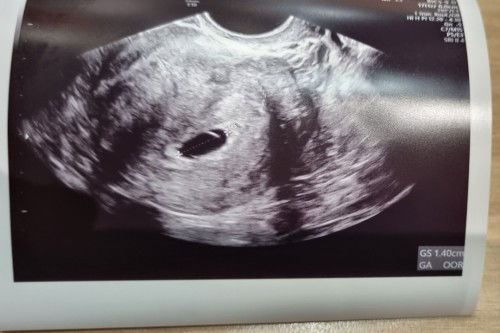

1st pregnancy ultra sound

Base on LMP(7 Feb 2023) I suppose to be 7 weeks pregnant today. This morning, I notice light brown discharge and past few days had abdomen cramp... Today went for my 1st gynaecology appointment... Doctor did ultra sound and mention that base on scan, I'm only 4 weeks pregnant... Sac can be seen in the scan... doctor gave me dydrogesterone to support my pregnancy and help with the discharge... have to go back in 2 weeks time... feeling worried has I had previous miscarriage in Oct'22. Have anyone went through this b4?